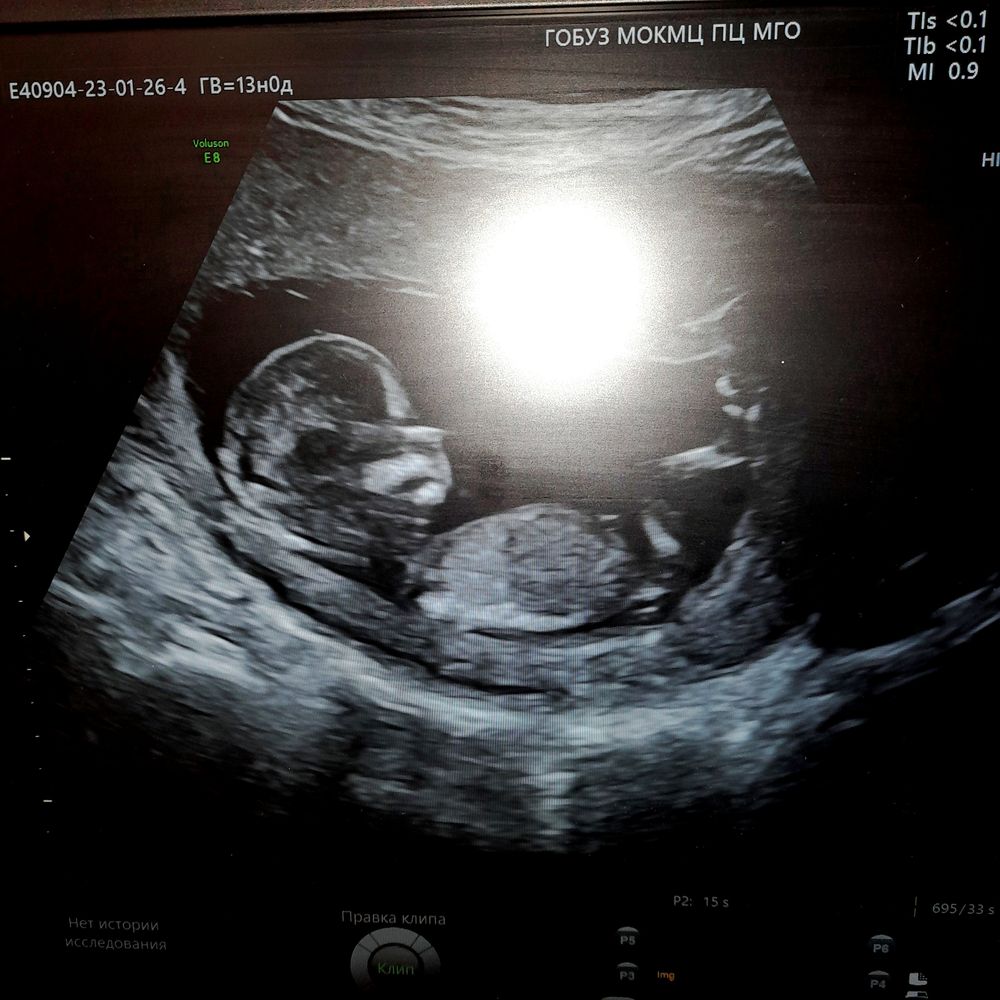

1й скрининг

Конечно же пацан)) у меня такие же были на первом скрининге) неделю назад ходила, подтвердили пацанов))) поздравляю 🫶🏼

Мальчик?)

Мальчишечка

А так можно увидеть ? Он же боком вроде нет ?

Оксана , как раз боком и можно точно увидеть ) по крайней мере, я вижу)

Anima, ну то что торчит что то я вижу , думала это нога 😂я своего видела на 20 неделе и в другой позе , а на 12 не показали

Оксана , ахах 🤣 Смотря как лежит, и есть ли желание показывать свой корешок)))